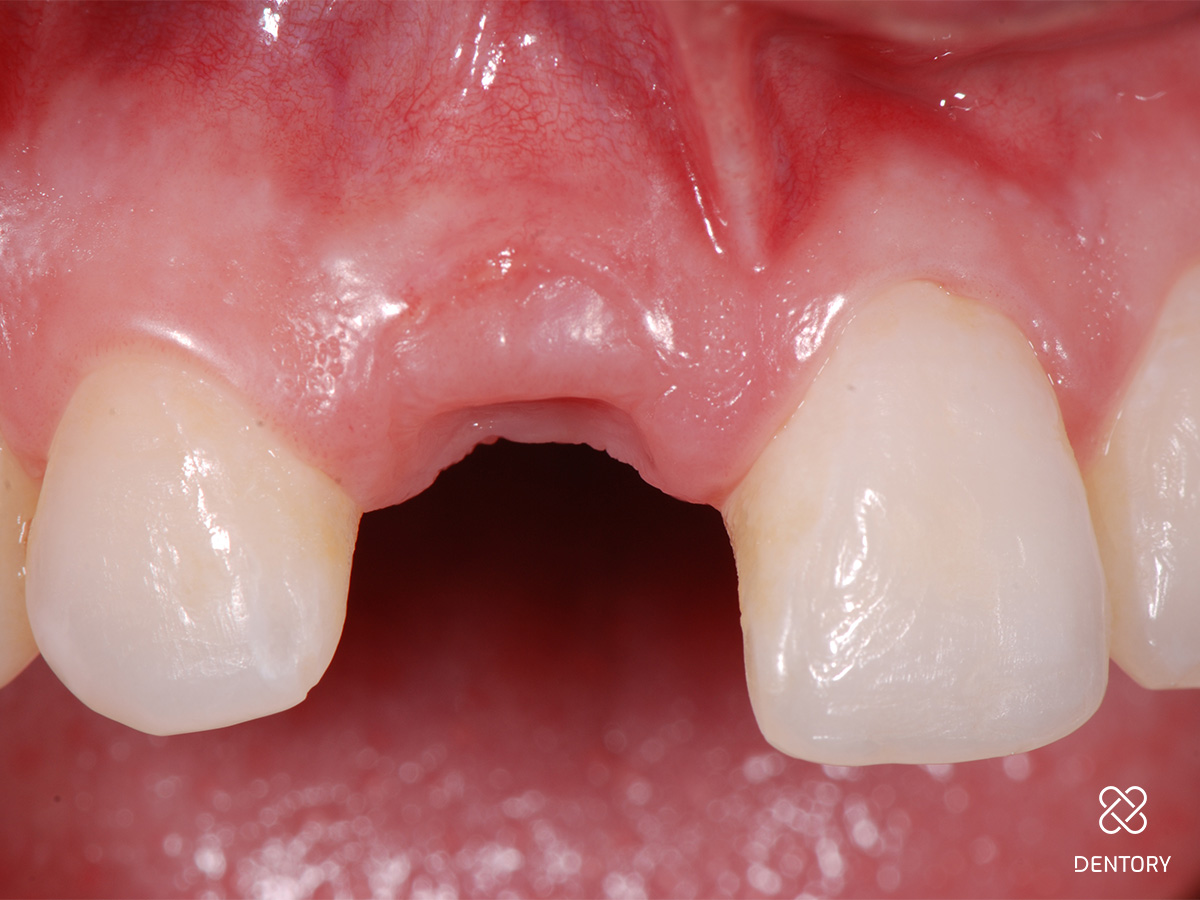

Abbildung 13

Nach 9 Tagen wurden die Nähte entfernt; es zeigt sich eine vollständige Einheilung des Transplantats mit gutem Volumenerhalt.

Abbildung 14

Ansicht okklusal.